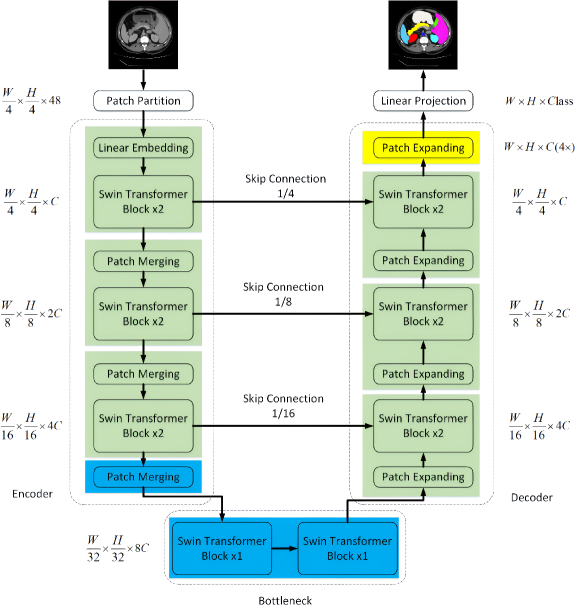

In computer vision, transformers can be divided into pure and hybrid ones. In pure transformers, the MSA modules are used in both the encoder and decoder. Hybrid transformer architectures fuse the ViTs with convolution modules in the encoder, bottleneck, decoder, or skip connections to combine information about the global context and local details (Azad et al., 2024). Swin-UNet is a pure transformer with a UNet-like architecture (Fig. 6) employing the Swin transformer block in the encoder, bottleneck, and decoder (Cao et al., 2023a). CTUNet is a hybrid network (Fig. 7) for segmentation of the pancreas parenchyma with 3D channel transformer blocks inserted into the skip connection of a 3D UNet (Chen and Wan, 2022). A pancreas attention module with a project and excite block was designed and added to each encoder to enhance the ability to extract context information, while cross attention was inserted between the output of each transformer and decoder to eliminate semantic inconsistency (Chen and Wan, 2022).